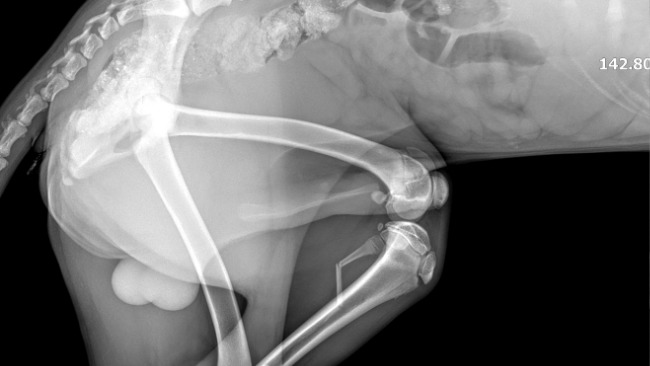

Harry to młodziutki (ok.1 roku) wyżełek po wypadku komunikacyjnym, w którym ucierpiały jego łapki. Łapka przednia wymaga natychmiastowej interwencji chirurgicznej!!!

Edit : W lecznicy podjęto decyzję o operowaniu obydwu łapek, koszt 3000 zł!!!

Dołączam zdjęcia rtg łapek, które ucierpiały oraz opis z lecznicy.